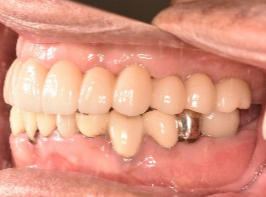

下顎左右奥の歯がないところに、インプラント治療を希望されて来院されました。X-Guideを使用し埋入しました。治療後「左右の奥歯でしっかり噛めてうれしいです。」と、とても喜んでくださいました。

インプラント3本:¥363,000×3本=¥1,089,000(税込)